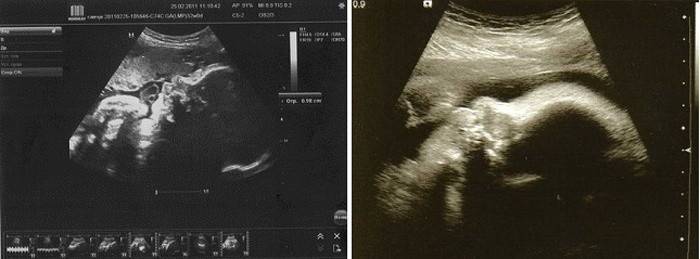

Badanie ultrasonograficzne (Uzi)

W okresie 32–34 tygodni ciąży zaleca się trzecie badanie ultrasonograficzne płodu, które jest konieczne w celu wykrycia późnych wad rozwojowych płodu, problemów ze ścianami macicy, łożyska i ustalenia dalszych taktyk zarządzania ciążą i planowania porodu. Przede wszystkim w badaniu ultrasonograficznym określa się prezentację płodu - głowę lub miednicę, z prezentacją głowy określa się, gdzie odwrócona jest tylna część płodu. Jest to konieczne, aby zdecydować, czy poród zostanie dostarczony naturalnym kanałem porodowym, czy też konieczne będzie cięcie cesarskie.

Ultradźwięki są odszyfrowywane przez lekarza, który ocenia główne wskaźniki ultradźwięków:

- szacowany wzrost i waga płodu, określa termin planowanego porodu,

- Wygląda na obwód głowy i klatki piersiowej, długość dużych kości

- ocenia strukturę i pracę narządów wewnętrznych, zwłaszcza nerek i serca, określa częstość akcji serca i przepływ krwi w sercu.

- w razie potrzeby wykonuje się również dopplerometrię płodu.

- Ponadto dokonuje się oceny ilości i charakteru płynu owodniowego, stanu ścian macicy, wielkości, wysokości dna macicy, stanu szyjki macicy, położenia łożyska i jego stanu, a także długości pępowiny i stanu jego naczyń. W tym okresie możliwe jest przeprowadzenie USG 3D, ale cały płód nie będzie widoczny na monitorze, ponieważ dziecko jest już wystarczająco duże i można zobaczyć tylko części ciała.